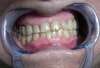

Une incisive du bas en avant la géne, ainsi qu'une couronne métallique à gauche sur une prémolaire.

Mais ce qui gêne le plus notre patiente, ceux sont ses incisives du haut usées et fissurées.